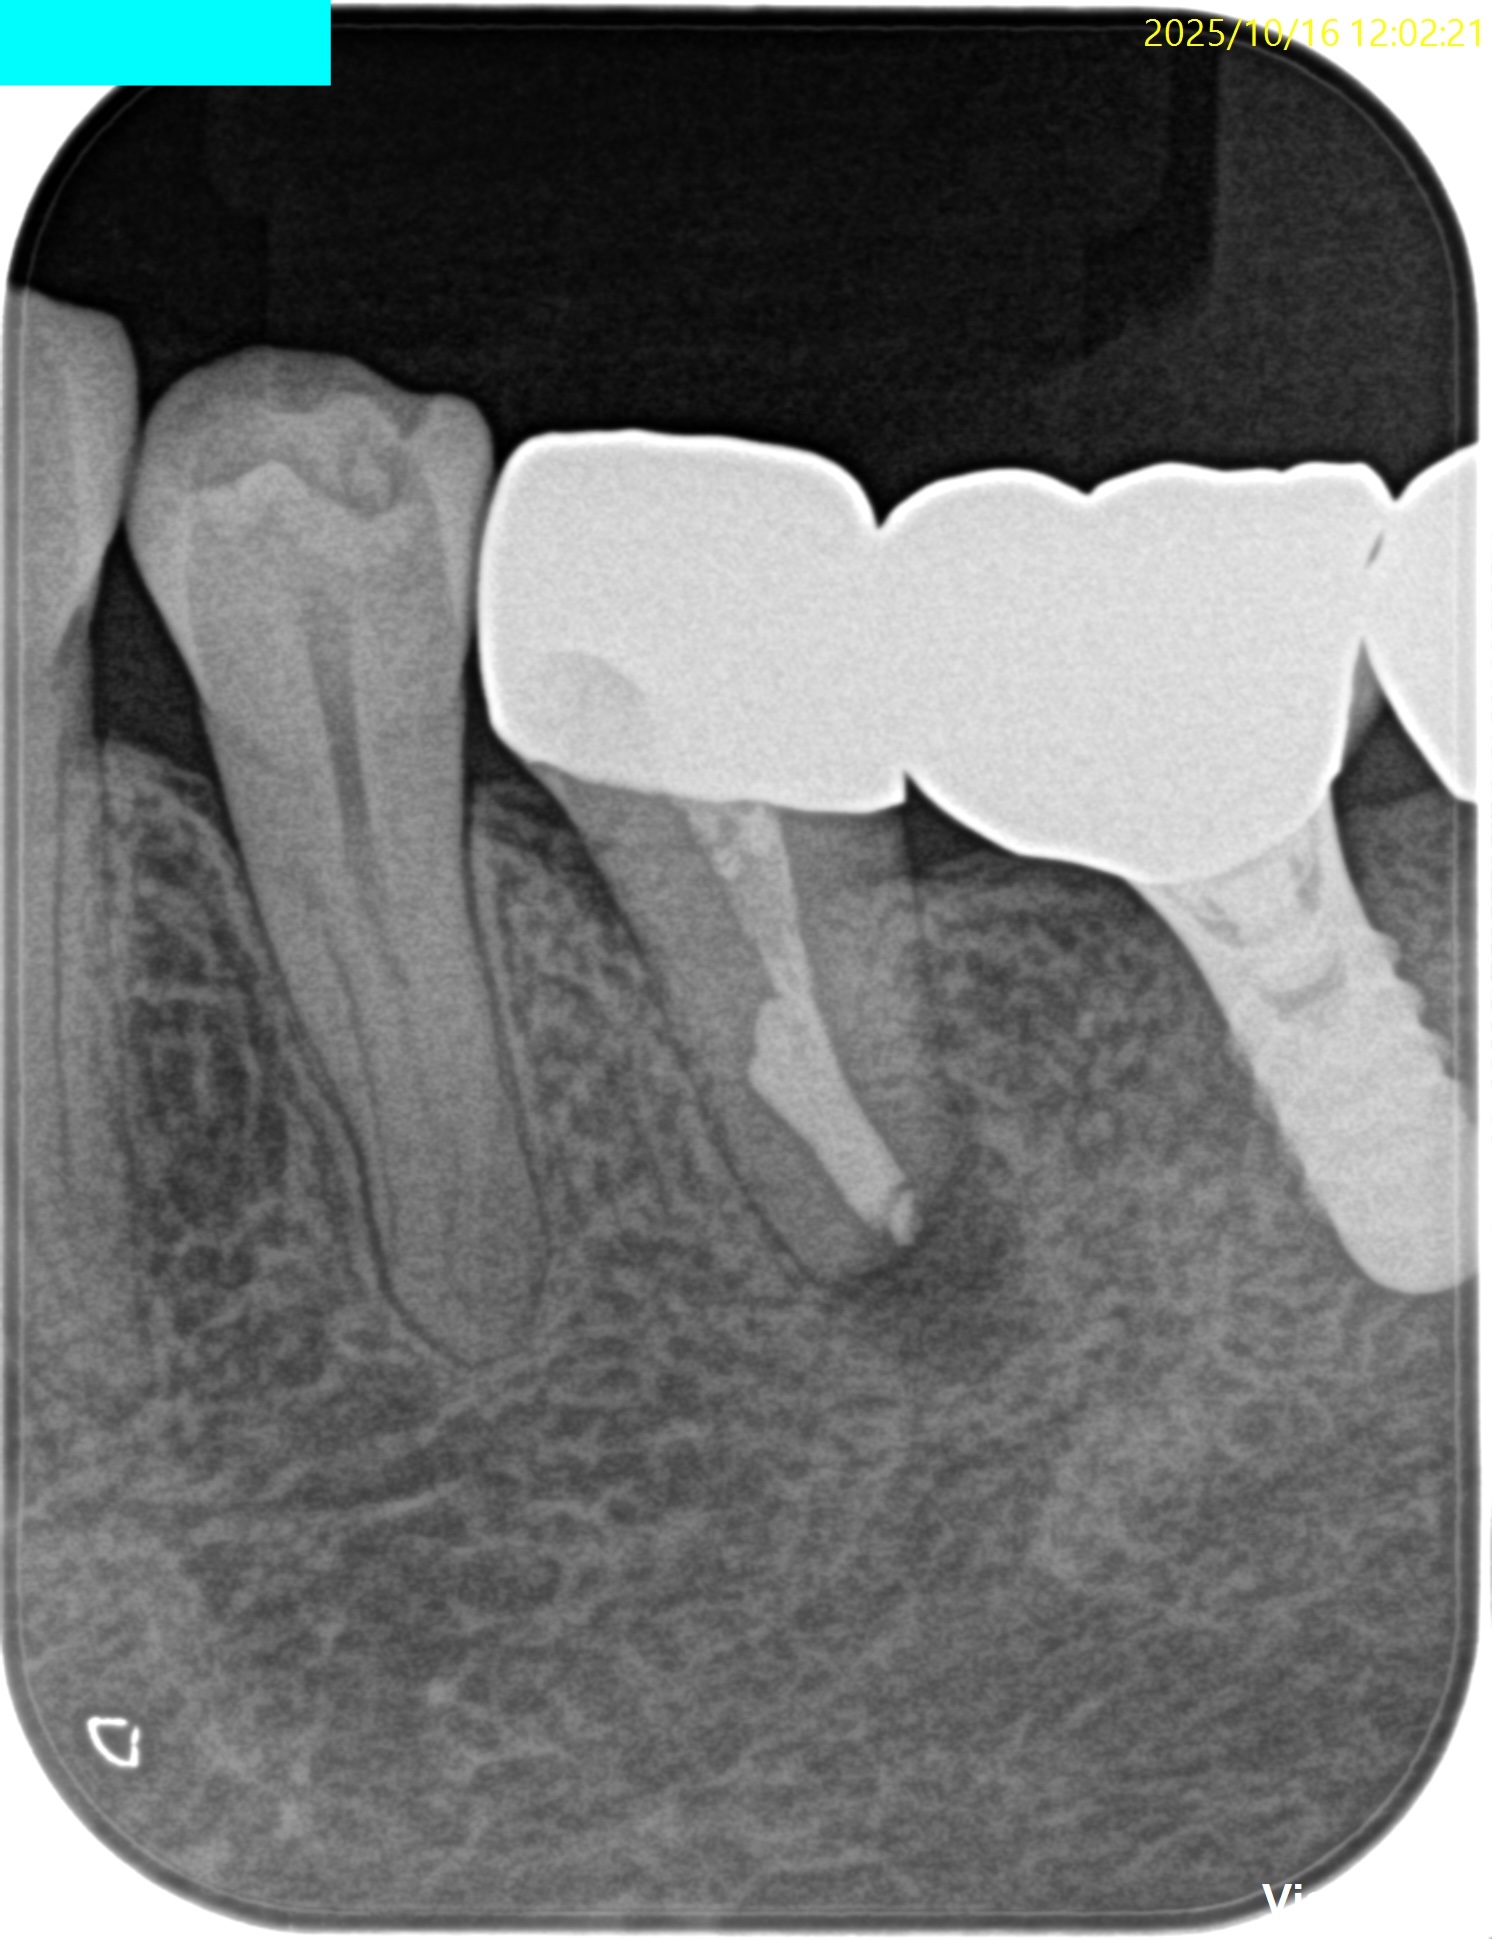

口腔外でApicoectomyを行い、

PAで状態確認し、問題がないことを確かめたのちに、

抜歯窩へ戻した。

術後のPA, CBCTは以下である。

問題はないだろう。